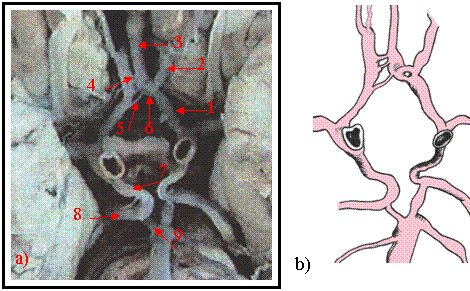

Cazul - 1- [ figura nr. 9.1 a) si b).]

Figura 9.1 Artera comunicanta anterioara

a) - artera comunicanta anterioanta accesorie

b) b) - prezentare schematica

La acest caz este semnalata o artera comunicanta anterioara accesorie cu diametrul de 0,5mm., lungime de 5mm. Un vas cu diametrul sub 1mm. in literatura este considerat nefunctional totusi de la aceasta comunicanta emerg vase pentru fata superioara a chiasmei optice.

Cazul -2 [figura 9.2 a) si b)]

La acest caz artera cerebrala anterioara stanga in portiunea distala a segmentului A-1 apare sub forma unei trifurcatii, prezentand o ramura laterala si doua ramuri mai subtiri cu orientare mediala. Ramura laterala, bine calibrata, urmeaza traiectul segmentului A-2 al arterei cerebrale anterioare. Ramurile mediale se anastomozeaza, formeaza o butoniera vasculara si se continua sub forma de artera cerebrala mediana. Inchiderea poligonului Willis in partea anterioara se realizeaza prin mai multe artere comunicante anterioare de calibru redus, avand dispozitie scalariforma

Figura 9.2 a) vasele poligonului Willis disecate pe encefal

b) prezentare schematica

1-.segmentul A-1 al cerebralei anterioare stangi. 2.-.segmentul A-2 al cerebralei anterioare stangi. 3-.artera cerebrala anterioara mediana. 4.-artere comunicante anterioare. 5- prima comunicanta anterioara. 6.- butoniera arteriala. 7.- comunicanta posterioara. 8.- segmentul P-2 al cerebralei posterioare drepte. 9.-.segmentul P-1 al cerebralei posterioare drepte.

Prima comunicanta, mai lunga, realizeaza anastomoza intre artera cerebrala anterioara dreapta cu prima portiune din ramificatia cerebralei anterioare stangi. Urmatoarele trei comunicante anterioare, foarte scurte, realizeaza anastomoza cerebralei anterioare drepte cu artera cerebrala mediana. In sectorul posterior al poligonului arterele comunicante posterioare aproape simetrice, de calibru peste mediu, se continua cu segmentul P-2 al cerebralei posterioare. Segmentul P-1 al cerebralei posterioare, de lungime redusa bilateral, ramane ca o punte anastomotica intre trunchiul arterial bazilar si artera comunicanta posterioara.